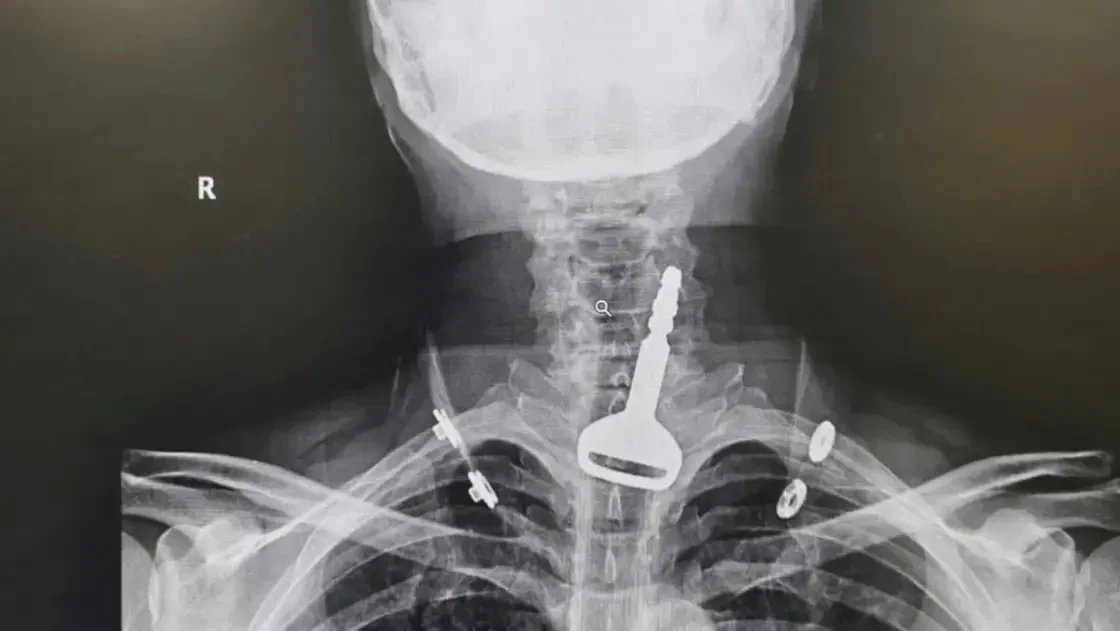

Саудия Арабистонида шифокорлар 49 ёшли эркакнинг томоғига тиқилиб қолган калитни олиб ташлашга муваффақ бўлди. Бу ҳақда Al-Arabiya хабар берди...